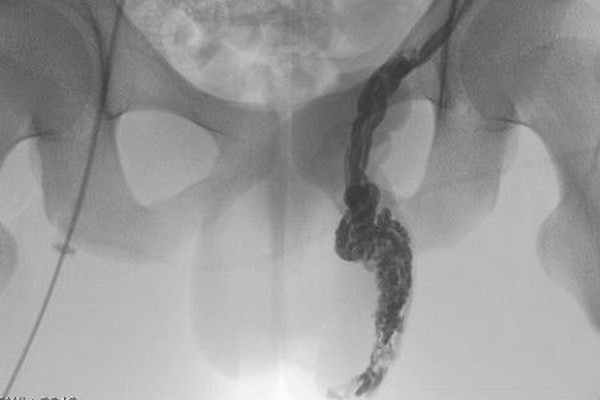

4. Флебография для мужчин

Практикуется для диагностики и контроля над эффективностью лечебных мероприятий варикоцеле. Вследствие высокого риска травмирования тканей, данную методику применяют редко.

После использования местной анестезии осуществляют введения контрастного раствора через вену в корне мошонки. Доктор посредством рентген-оборудования следит за скоростью распространения препарата в зоне паха.

При помощи рассматриваемого вида диагностики возможно выяснить точный диаметр семенной вены и ее структуру.